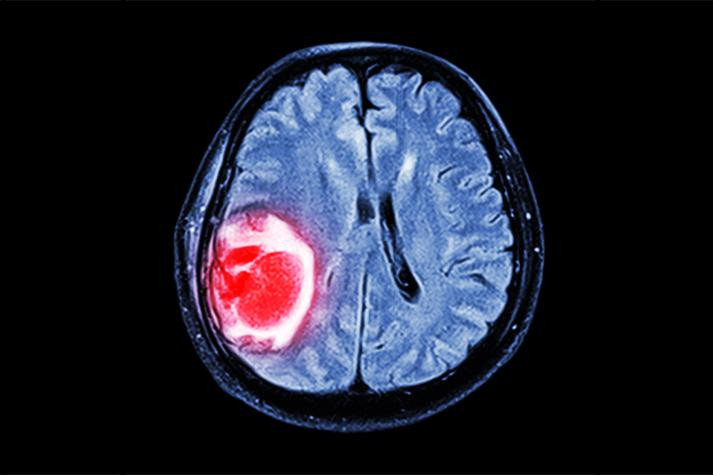

检查结果让人震惊:颅内肿瘤,已压迫听神经,且病情进入晚期。

临床上,除了耳部疾病本身(如中耳炎、耳硬化症等),脑部病变,尤其是听神经瘤、脑膜瘤、颅内高压等,都可能以耳鸣为“首发症状”。长期单侧耳鸣、伴有听力下降、眩晕、头痛,更应高度警惕。

很多人没意识到,脑瘤早期可以没有明显疼痛,但会通过“功能受损”发出信号。比如听神经瘤,往往从单侧耳鸣、听力下降开始,随着肿瘤长大压迫周围脑组织,逐渐出现面部麻木、走路不稳、视物模糊等症状。如果此时仍未就医,就有可能错过最佳干预期。